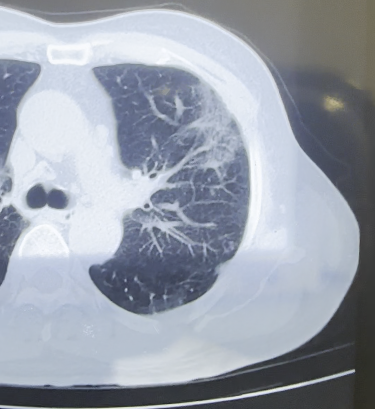

女,63岁,肺粘液腺癌一例